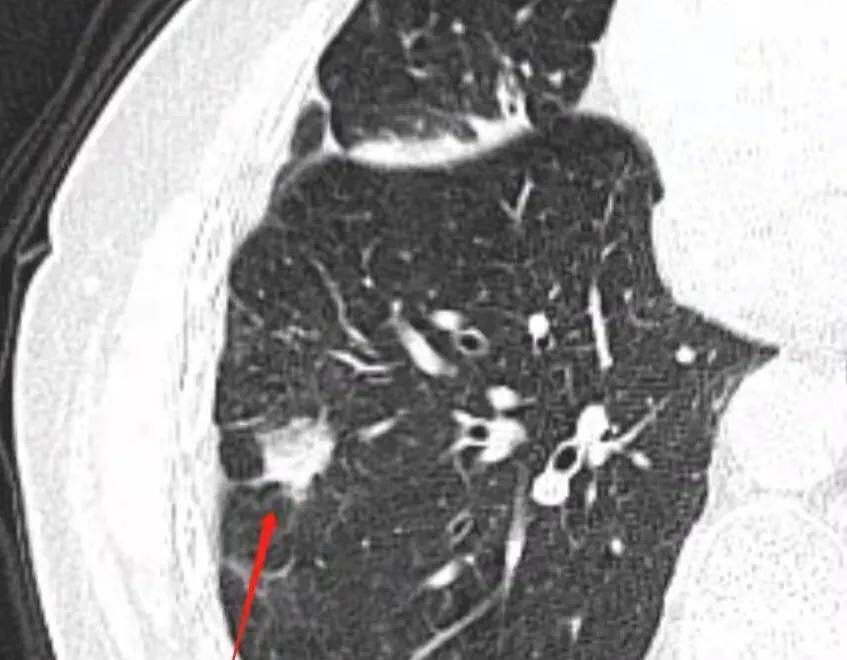

75岁的张大爷最近被诊断出混合磨玻璃肺结节变实性结节,医生怀疑可能是肺癌。面对这个消息,张大爷和家人陷入了深深的焦虑和无助之中。然而,随着医学的进步,老年肺癌患者有了新的希望 - “带瘤生存”。

实现“带瘤生存”需要多方面的努力。首先,精准诊断至关重要。正如上海市胸科医院肿瘤外科副主任医师周谦君所言:“肺癌的临床表现大相径庭,病灶大小、形态、数量、生长部位、病理类型、分子分型都不同,这些都是影响选择诊治方法的关键因素。”因此,医生需要通过多学科会诊,为每位患者制定个性化的治疗方案。